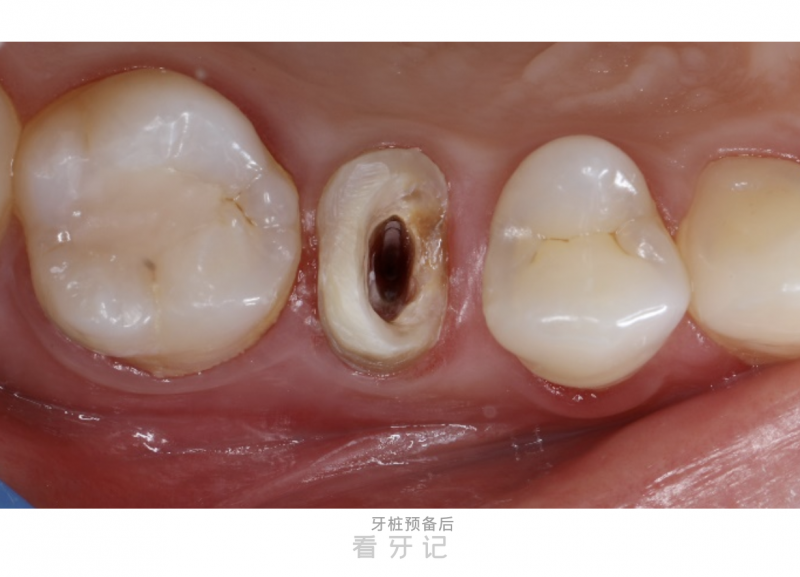

第2次就诊:戴牙桩+牙体预备。

医生将定制好的牙桩置入根管内,使用粘接剂将牙桩和牙齿紧密连接,并对牙体进行修整,为最终的全瓷冠预留足够的空间。必要时,医生还会制作一个临时冠,维持牙齿的美观与功能,避免影响患者的社交活动。